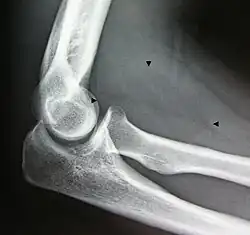

X-ray of a lipoma -

X-ray showing lipoma -

Bone formation may be seen in both lipomas[26] and liposarcomas (a well-differentiated one pictured).